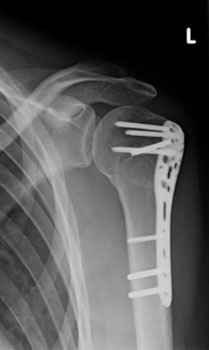

In diesem Fall ist eine winkelstabilen Plattenosteosynthese indiziert. Durch die winkelstabile Schraubenverankerung im Plattenlager und divergierenden Schraubenverlauf, welcher die ganze Breite des Kopffragmentes nutzt, wird eine hohe primäre Stabilität erreicht. Dies ermöglicht eine frühfunktionelle Übungsstabilität bei gleichzeitiger

Schmerzreduktion. |